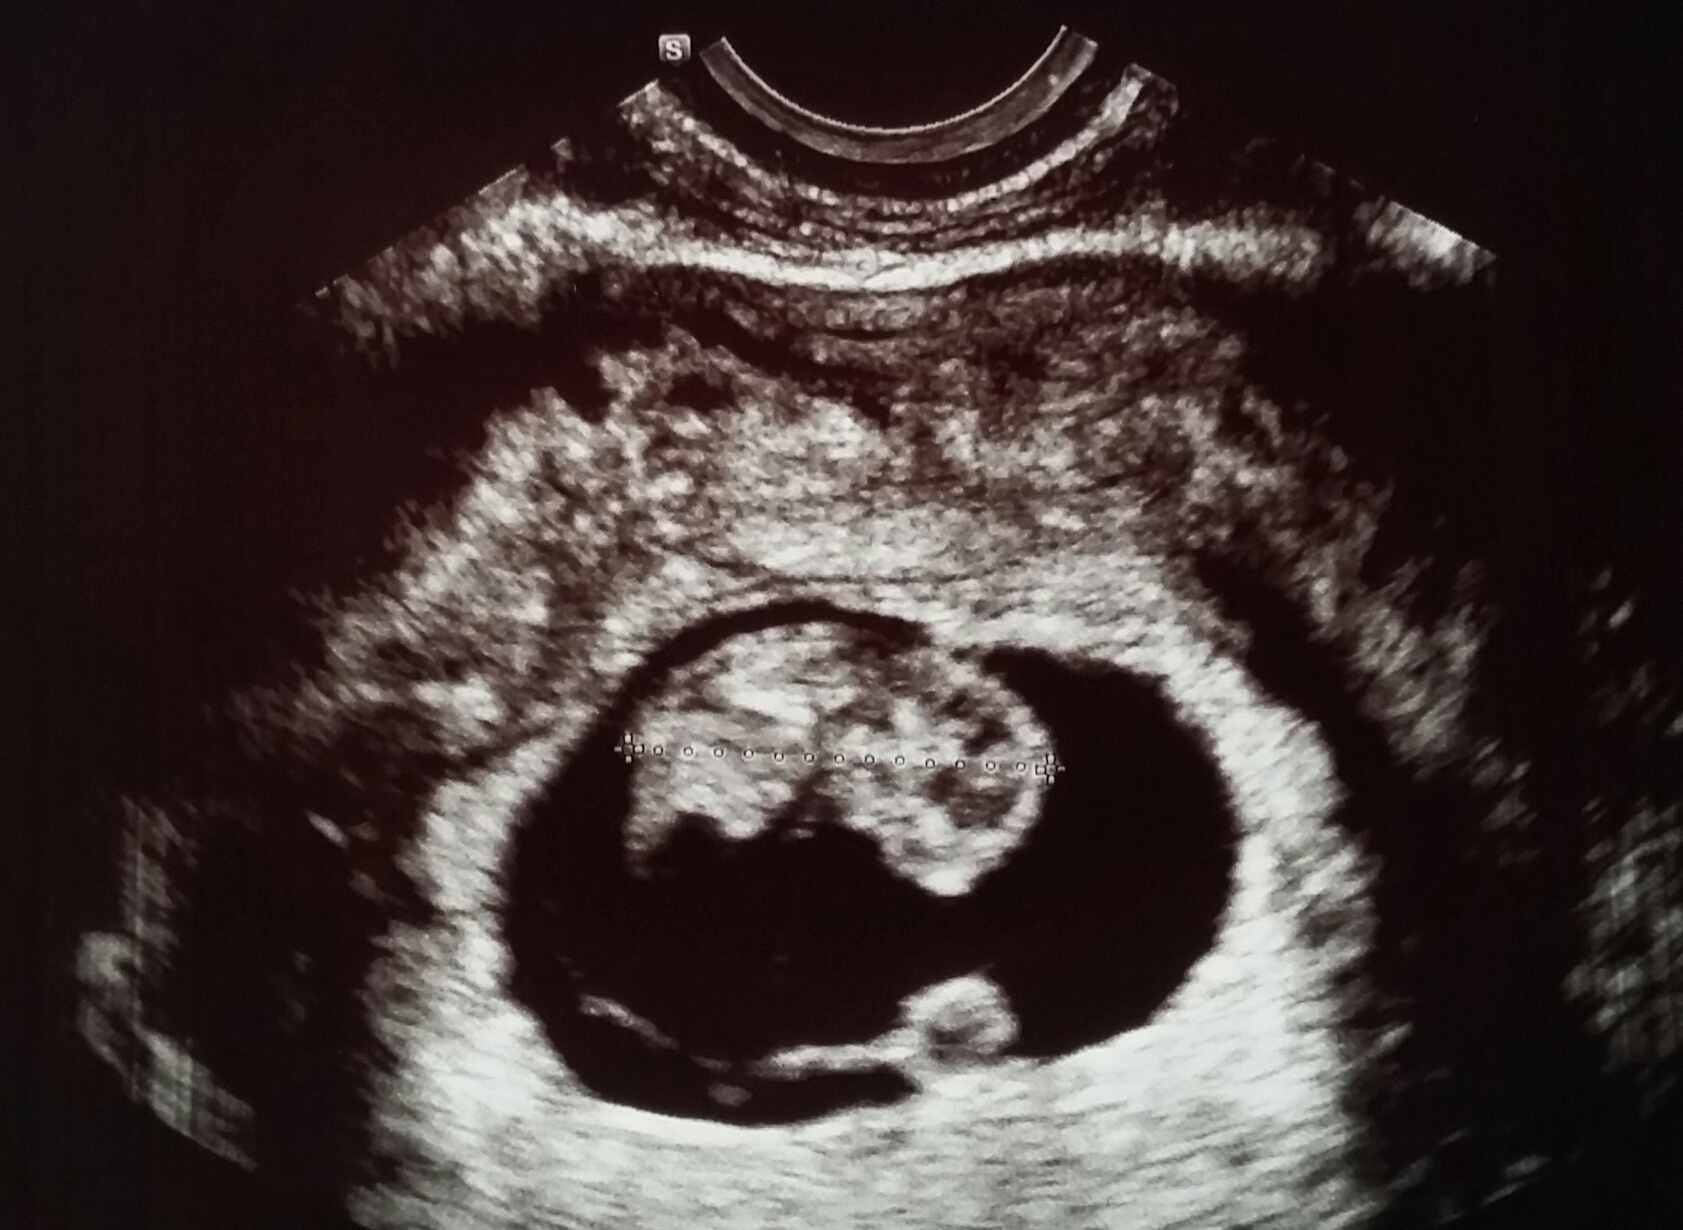

8w6d! Transvaginal. He/she was a little wiggle worm when the Dr first turned the machine on